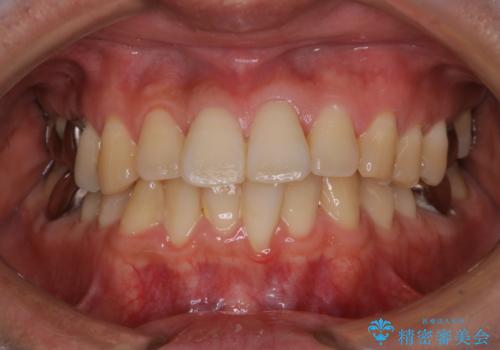

- マスクの着用により、口臭が気になるためクリーニングをしてほしいとのことでした。PMTC60分コースを行いました。

バイオフィルム(細菌の塊)を破壊し、歯の表面をツルツルにすることでお口の中の細菌数を減らし歯周病のリスクが定着するのを防ぎます。更に、歯に新しい汚れがつきにくい状態になります。

バイオフィルムが除去されると、ご自身本来の歯の表面になります。PMTCをすることで口臭予防にもなり、定期的に行うことが大切です。